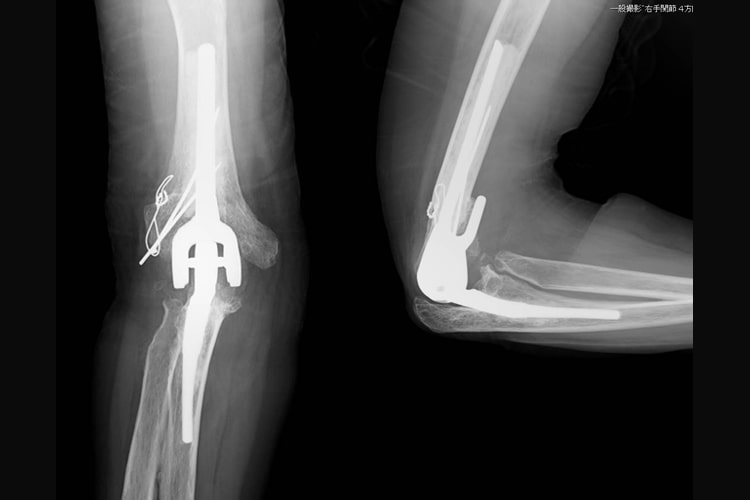

表面置換型人工肘関節写真

表面置換型人工肘関節

半拘束型人工肘関節写真

半拘束型人工肘関節

関節リウマチにより手や指、肘の関節が破壊されて変形や疼痛が生じます。滑膜炎により指の腱が切れてしまうこともあります。関節リウマチの治療の基本は内服加療ですが、骨破壊が生じてしまったり、腱が断裂した場合は手術が必要です。

腱が切れた場合は腱移行や腱移植を行って治療します。手の腫れや痛みが持続した場合、関節破壊の程度に合わせて滑膜切除、関節形成、関節固定を追加します。最近は人工手関節置換術を行う場合もあります。指や肘の関節リウマチについても、腫れや痛みが持続する場合は人工関節置換術を行うことで生活レベルの向上が期待できます。